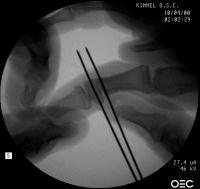

Intraoperative fluoroscopy. The mass:

Click for larger image

Osteotomy planning: proximal pin parallel to the proximal joint line, distal pin parallel to the distal joint line:

Pins were used as saw blade alignment guides: